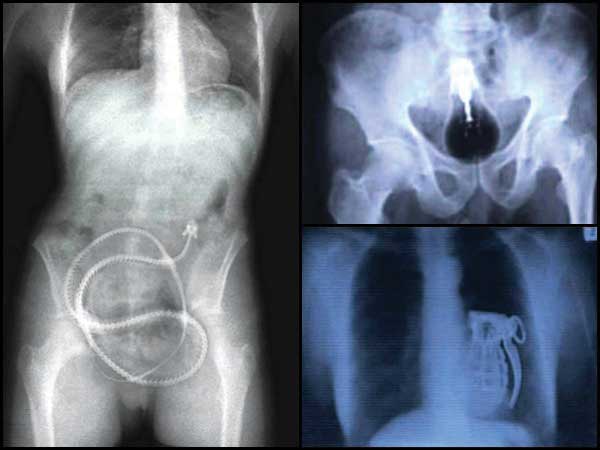

Live Eel

Lolz! This is the funniest of all. A man from China admitted himself to a hospital when he accidentally got a live eel stuck inside his anus. He said that he was inspired by the porno world so much that he wanted to try something unique. Doctors claim that the eel was alive when the man was being operated, but it died shortly after it was removed.

Light Bulb

Okay, it is true that a light bulb was found in the large intestine of a Pakistani prisoner. Now, you can let your imagination flow as to how did it even land there in the first place!